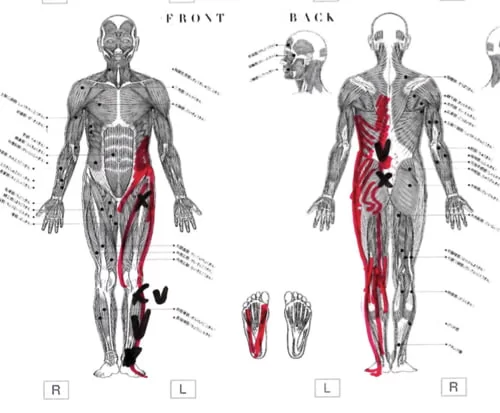

2か月前から左臀部、ふともも、ふくらはぎ、足首が痛み

痛みの場所はここ。

そして脚の前側にも痛み

膝下のここにも痛み。

そして足先はシビレがある状態でした。

こんな感じで筋肉や腱の硬直やヨジレがありました。